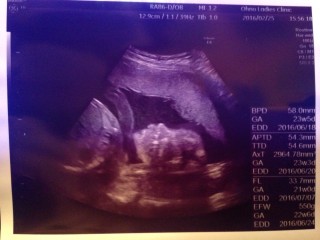

写真:22w0d:さきさん:体やらかい

分かりづらいかも知れませんが、左手を頭(おでこ?)に添えながら右手で指しゃぶりをしているところです♪ 口をチュパチュパと動かしており感動。 まだ小さいだけで、すっかり人間ですね(^∀^) 体重は566gとのことで、少し大きめな男の子♪ ずっと逆子のようで、膀胱付近をグイグイされています(´д`;)